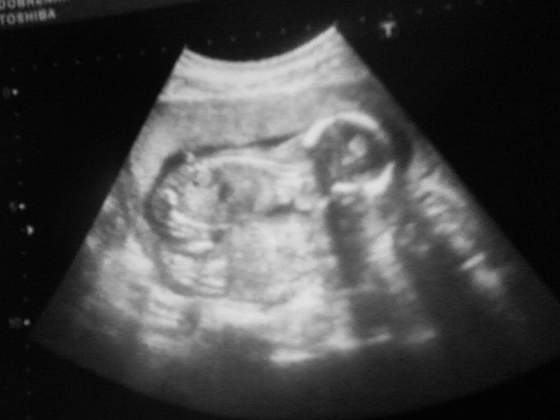

no dobra, ja jade na usg jutro na 9.15, u Was bedzie 10.15chyba czuje od jakiejs godziny wielki niepokoj.. poogladalam zdjecia ktore dalyscie i zastanawiam sie jak nasza dzidzia

Kruszki a to dopiero pierwsze usg Twoje? bo widze ze juz w 15 tyg jestes to powinnas miec to pierwsze juz zrobione, chyba ze tak dbaja tam o was i macie czesciej ?

kurcze chciałabym juz wiedziec kto mieszka pod serduszkiem , strasznie byłam smutna po tej walentynkowej wizycie bo tak naprawde bede sie znów łudzić kolejny miesiac ze to córa a w koncu okaże sie ze synek, no rozum mówi ze nie ważne co ale serduszko podpowiada dziewczynkę